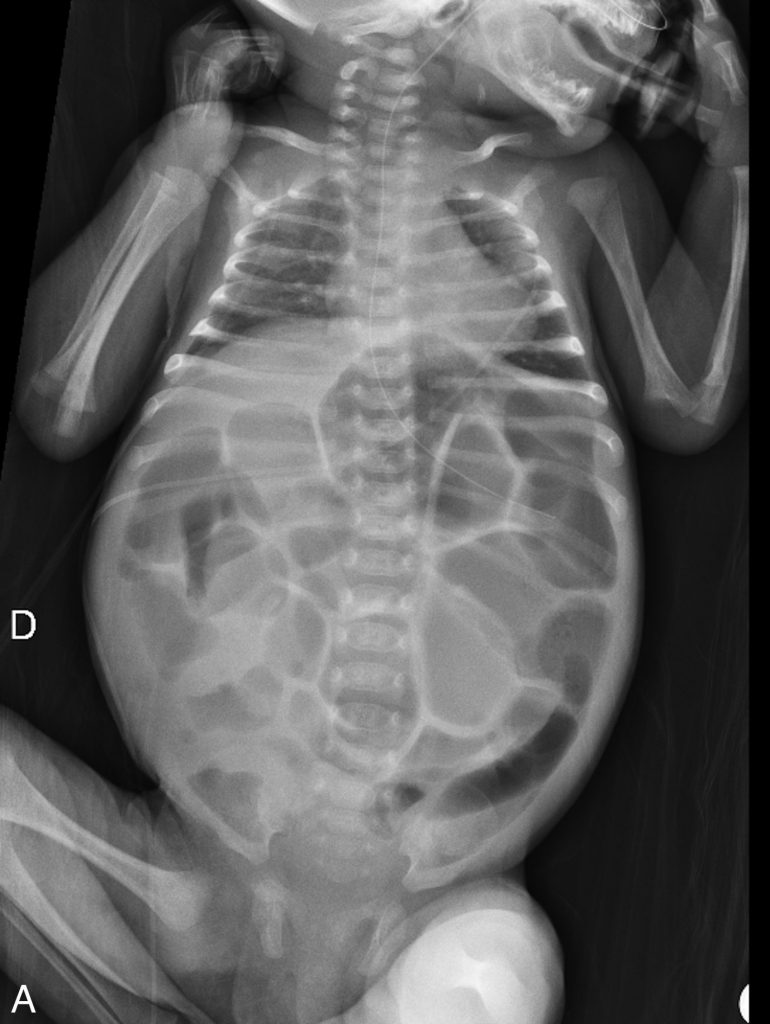

En période néonatale, l’exploration en imagerie d’un syndrome occlusif repose sur le couple ASP (abdomen sans préparation en position couchée) et échographie abdominale, complété par l’opacification du côlon par lavement aux hydrosolubles iodés. L’échographie confirme le syndrome occlusif : présence d’anses dilatées (distension liquidienne) et d’anses plates.

Elle est l’examen de choix pour l’étiologie la plus urgente (volvulus du grêle sur malrotation digestive) et est utile pour les autres étiologies (atrésie du grêle, iléus méconial, bouchon méconial ou petit côlon gauche, maladie d’Hirschsprung et malformation anorectale). Elle permet de préciser le contenu liquidien ou méconial en amont et dans la zone de transition et d’évaluer les signes de gravité (souffrance digestive). L’ASP montre la distention aérique (jamais de niveaux hydroaériques car il est fait en décubitus) (figure.14.4). Le lavement aux hydrosolubles aide au diagnostic des étiologies sus-citées et est thérapeutique dans le bouchon méconial.

Fig. 14.4 Abdomen sans préparation (ASP) couché d’un nourrisson de 5 semaines (A) présentant un ballonnement abdominal et des vomissements, et lavement par voie basse aux produits de contraste iodés hydrosolubles (B).

Il existe sur l’ASP une distension aérique diffuse sous la forme d’hyperclartés larges — la distinction entre le grêle et le côlon n’est pas possible sur l’ASP chez le nouveau-né et le jeune nourrisson, contrairement à l’enfant. Le lavement aux hydrosolubles permet de confirmer qu’il n’existe pas d’anomalie de morphologie du cadre colique. L’occlusion est donc grêlique. Il s’agissait d’une occlusion du grêle sur une bride dans un contexte de laparoschisis opéré en néonatal.

Source : CERF, CNEBMN, 2022.